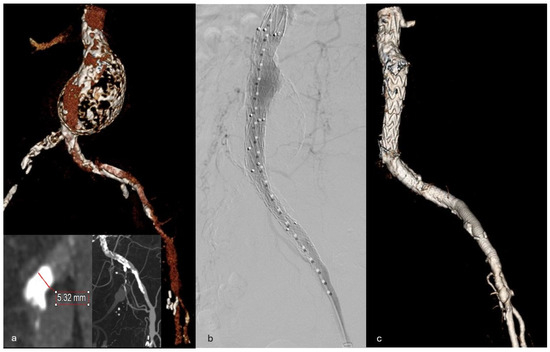

An 81-year-old male with a past medical history of peripheral arterial disease (PAD), coronary artery disease status post coronary stenting, stage three chronic kidney disease, and lung cancer for which he underwent a left pneumonectomy and right wedge resection presented to our clinic with an asymptomatic infrarenal AAA with extensive calcifications. He had a left superficial femoral artery (SFA) endarterectomy with a patch angioplasty performed in 2019 for claudication. After that procedure, his symptoms were controlled well, and he was surveilled with CTAs. His AAA had enlarged from 4.5 cm in 2021 to 5.5 cm in 2024. Imaging also showed a chronic occlusion of the right common and external iliac arteries (EIA) with reconstitution of flow to the SFA from collateral vessels, as well as severe tandem stenoses of the left CIA and EIA (Figure 1a). He was not a candidate for open repair due to comorbid conditions and significant aortic calcifications, precluding safe aortic clamping. Notably, his ABIs were 0.57/1.07 and he did not endorse any claudication symptoms.

Figure 1.

(a) Preoperative CTA 3D reconstruction of aortic aneurysm with calcified and diminutive left iliac artery. Inserts showing dense iliac calcification. (b) Aorto-uni-iliac (AUI) completion angiogram. (c) Postoperative CTA 3D reconstruction of AUI, VBX and Viabahn.